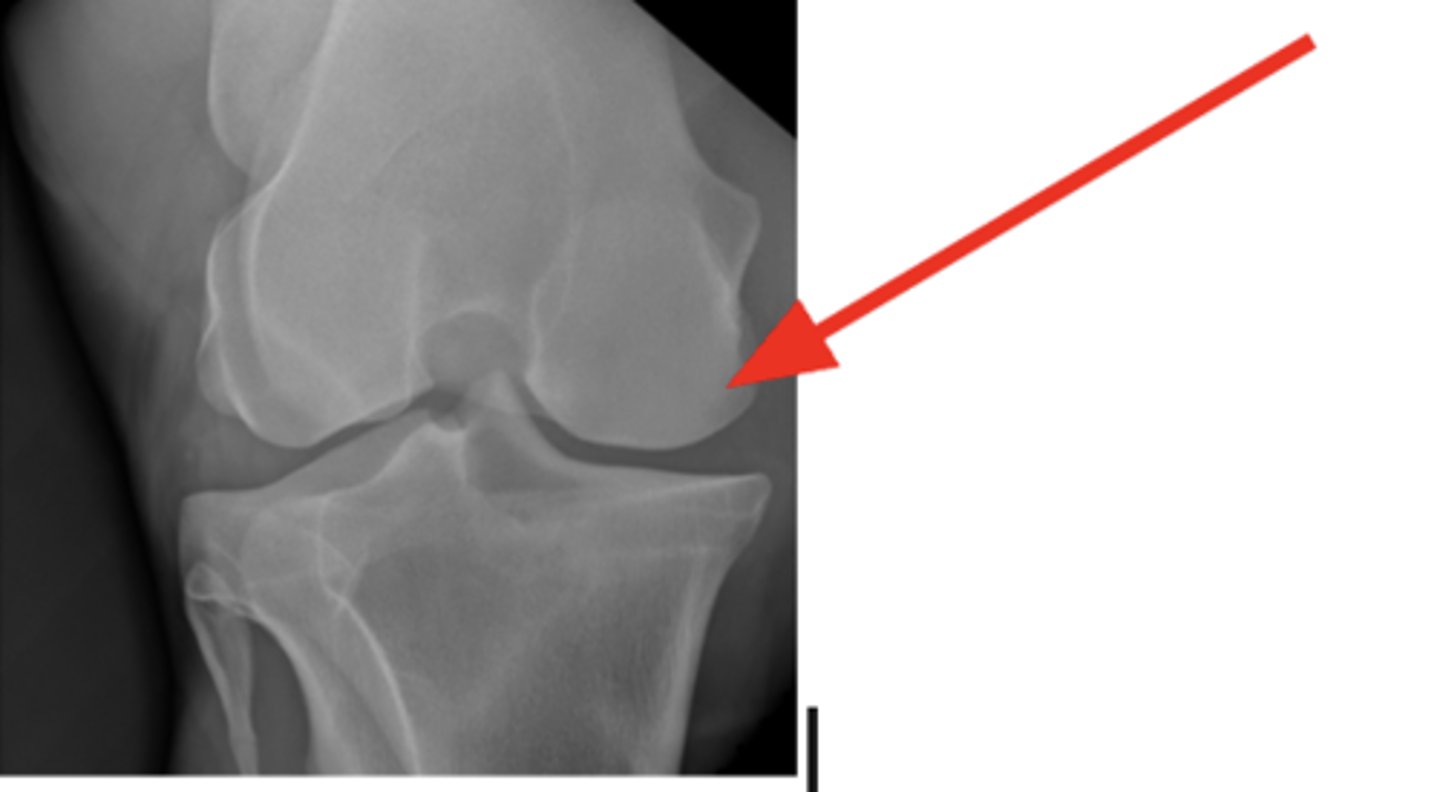

Medial femoral epicondyle

3 y/o horse lameness, effusion of stifle, where is the cyst?

Mineralized cartilaginous flap

What is a Common finding of OCD?